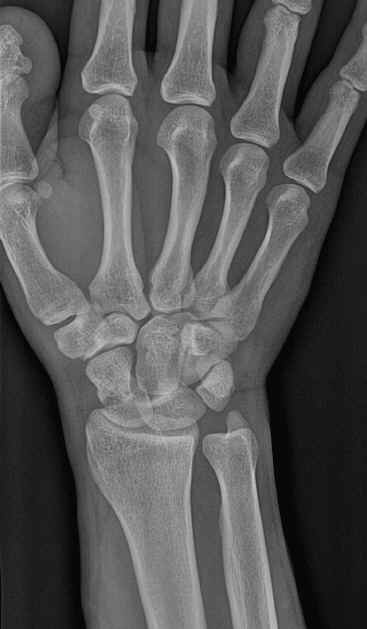

下面一例“月骨脱位病例”,请大家比较一下: